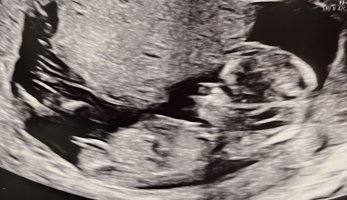

100% gutt12+2 i dag. Hvilket kjønn tror dere?

Vis vedlegget 456403

Det så veldig ut som en gutt![]()